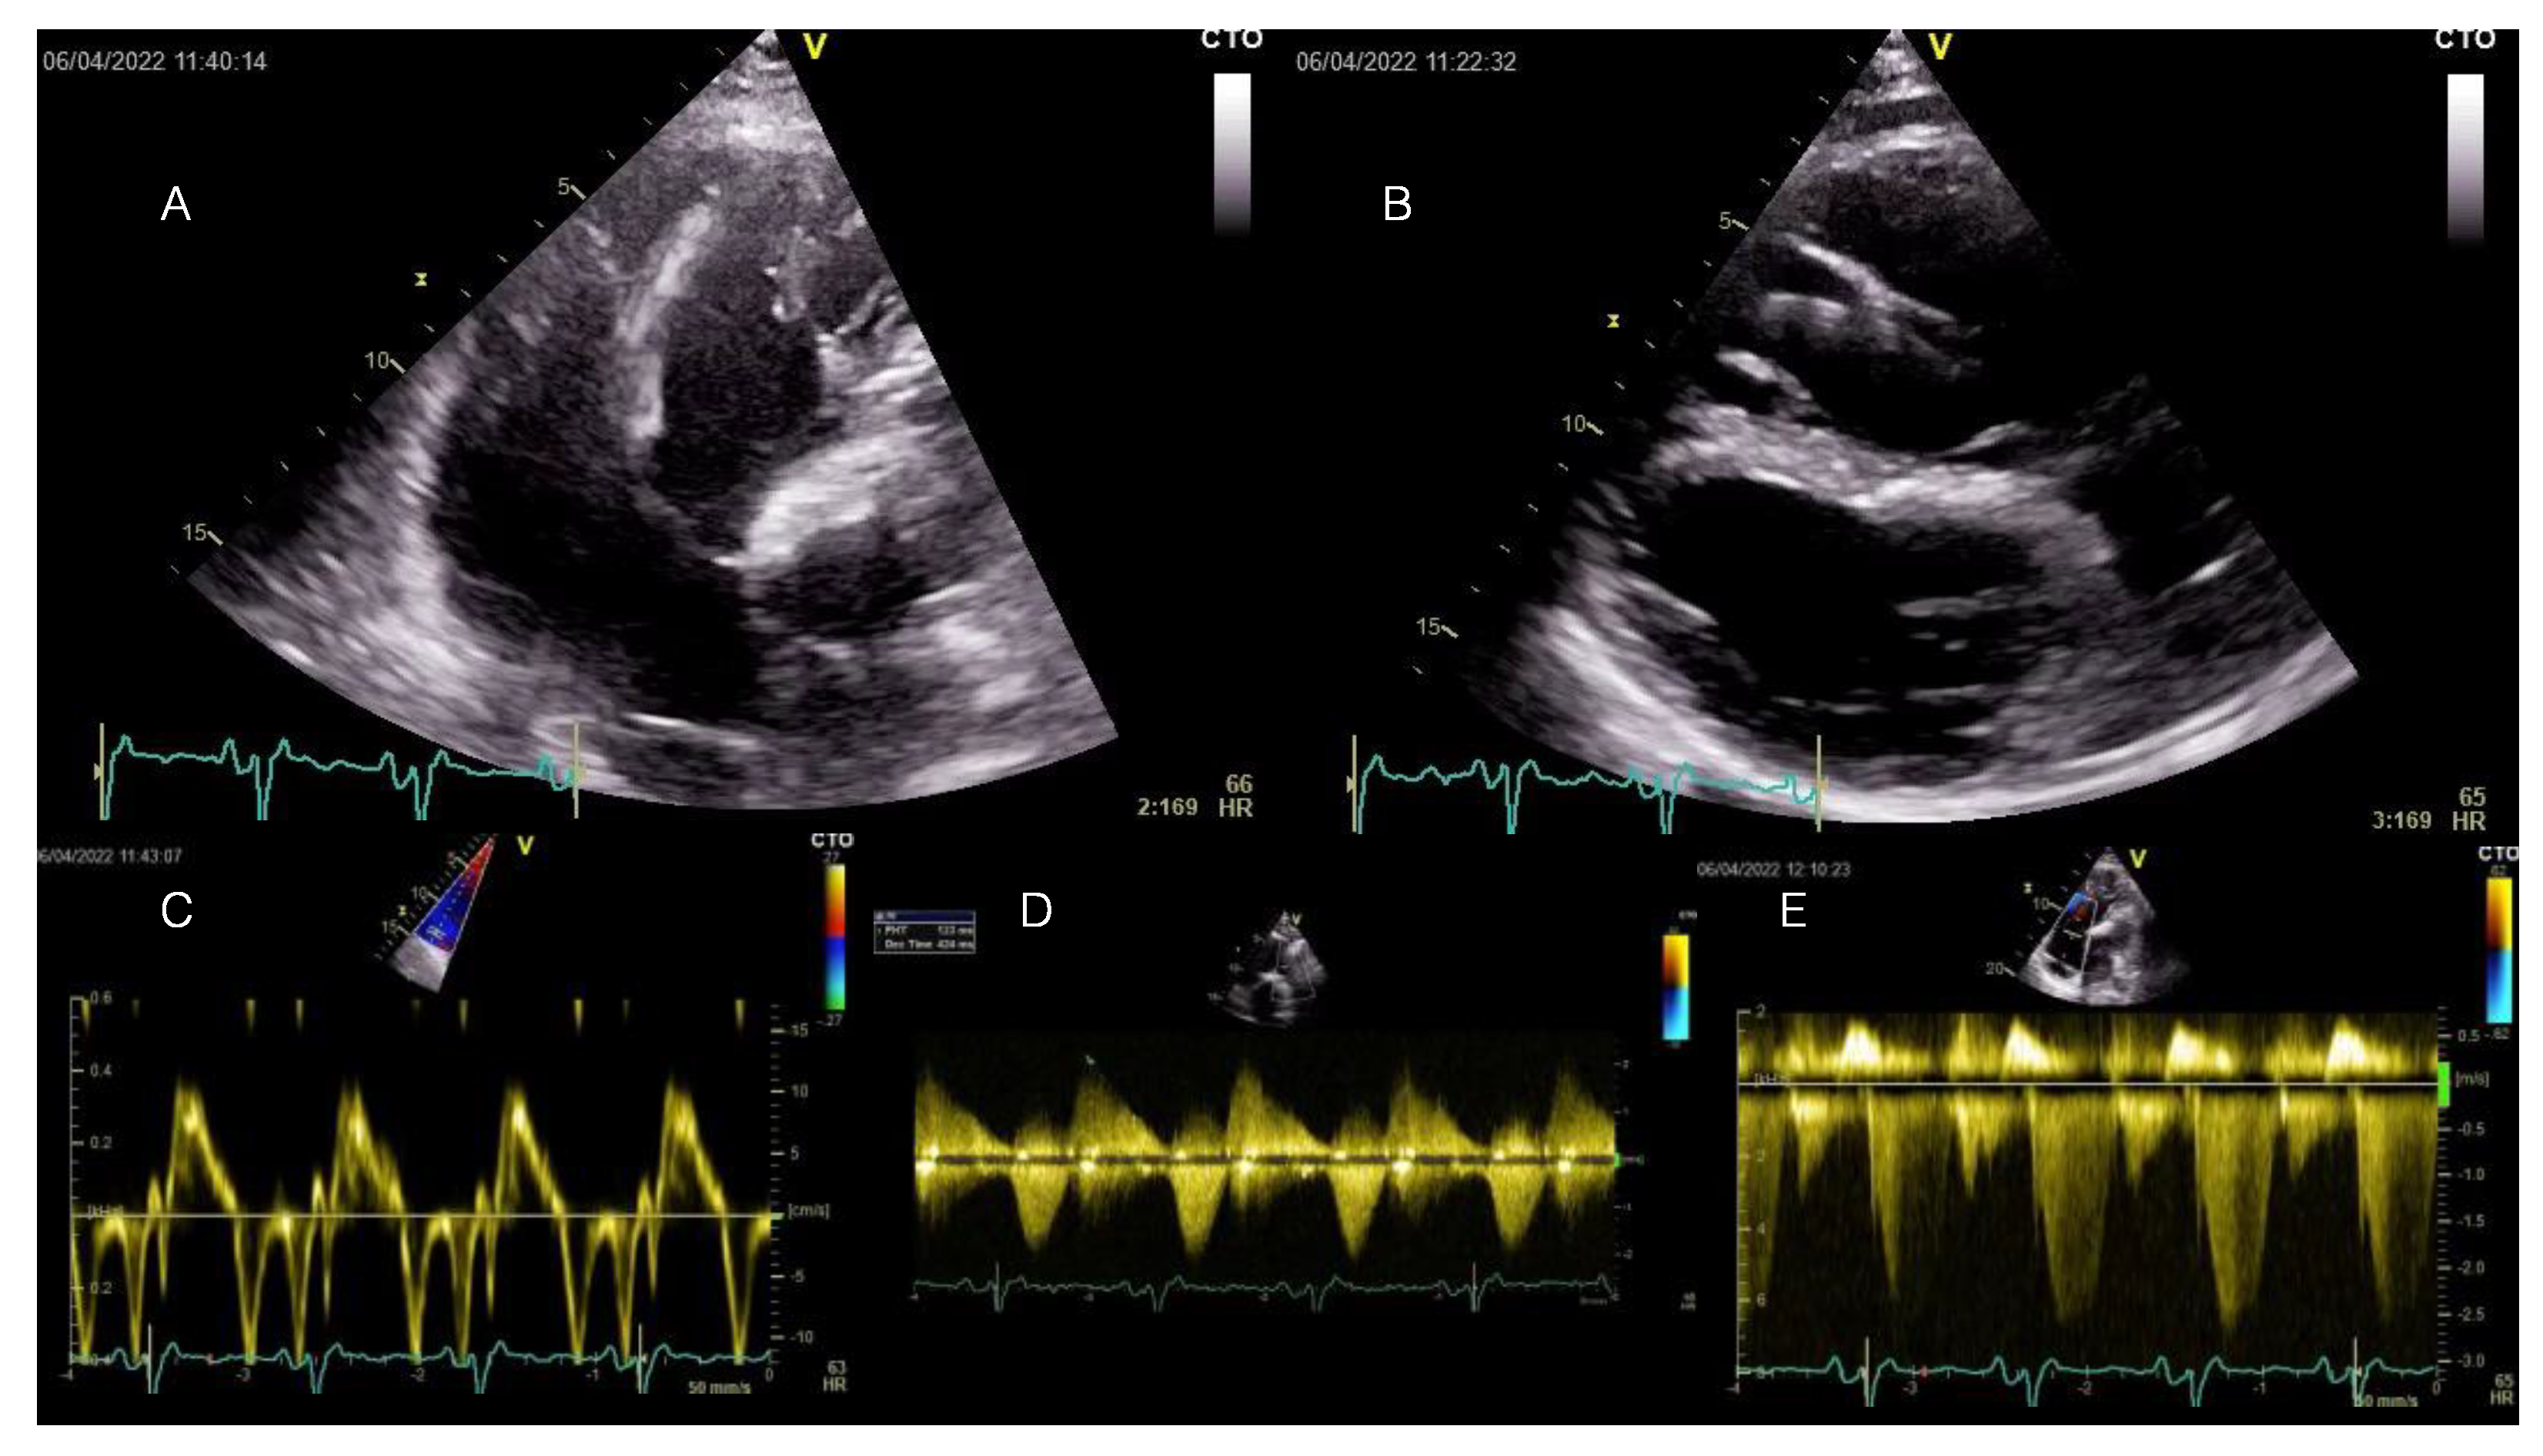

Figure 2.

Transthoracic echocardiography examination at current admission displaying RV enlargement and moderate-to-severe tricuspid regurgitation induced by severe pulmonary regurgitation at long-term follow-up after transannular patch-based surgical repair of TOF. All displayed images are interpreted in the patient’s clinical context below. TOF = Tetralogy of Fallot.

A transthoracic echocardiography showed RV dilation (diastolic area 60.8 sqcm, 64 mm basal diameter) and mild systolic dysfunction (FACVD 32%, TAPSE 17 mm, S’t 11 cm/s) (Figure 2A–C). The single-coil RV defibrillation lead is also visible in Figure 2A. Figure 2B demonstrates a paradoxical movement of the interventricular septum due to RV overload and severe pulmonary regurgitation (PR). Severe PR and mild pulmonary stenosis (Figure 2D) (PHT 123 ms, regurgitant jet > ⅔ of RVOT area, vena contracta 9 mm, EROA 70 mm2) were previously noted for which the patient was scheduled for transcatheter pulmonary valve replacement (PVR), considering the past episodes of systemic congestion. Moderate-to-severe functional tricuspid regurgitation with significant enlargement of the tricuspid annulus (53 mm) (Doppler CW tracing in Figure 2E). The LV was dilated (89 mL/sqm) and mildly diffusely hypokinetic with a biplane Simpson LVEF of 48%. There was no LV dysfunction prior to the occurrence of the PVCs. There was no residual shunt visible. A previous cardiac magnetic resonance (CMR) scan documented minimal fibrosis at the border of the right ventricular outflow tract (RVOT) and septal patches and severe RV dilation (209 mL/sqm). Coronary computed tomography angiography (CTPA) showed no significant coronary lesions.